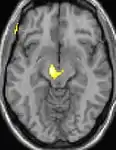

Positron emission tomography (PET) shows brain areas being activated during pain.

Voxel-based morphometry (VBM) shows brain area structural differences.

Positron emission tomography (PET) scans indicate the brain areas which are activated during attack only, compared to pain free periods. These pictures show brain areas that are active during pain in yellow/orange color (called "pain matrix"). The area in the center (in all three views) is specifically activated during CH only. The bottom row voxel-based morphometry (VBM) shows structural brain differences between individuals with and without CH; only a portion of the hypothalamus is different.[36]